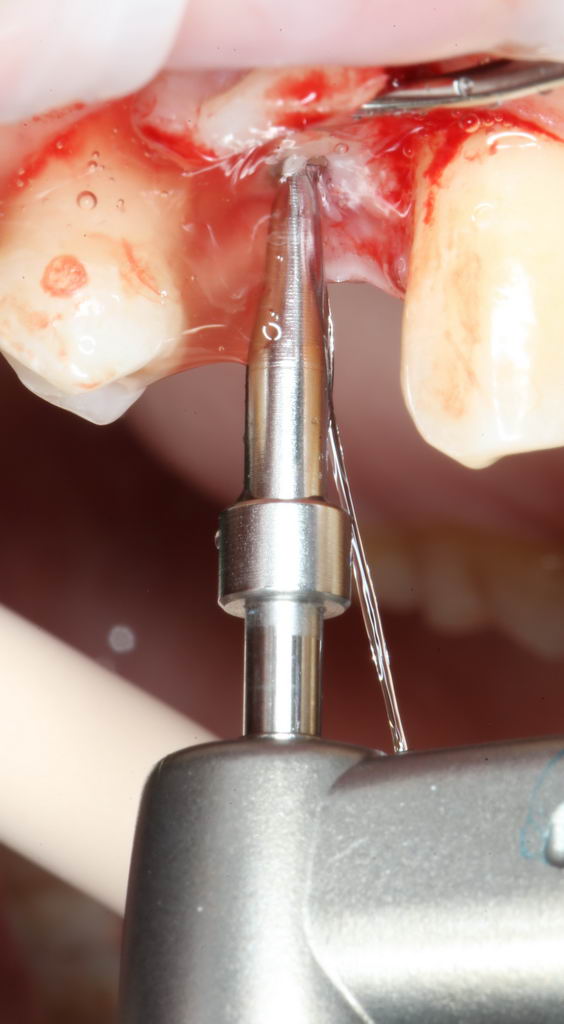

Подготовку лунки начинают с разметки. Делается это при помощи шаровидного бора:

Далее, с помощью пилотной фрезы диаметром 2 мм задаётся ось лунки будущего имплантата, которую контролируем с помощью пинов из набора Surgical Kit:

Далее, коль ось лунки задана правильно, нам остаётся лишь довести лунку до нужного диаметра. Для этого используются основные рабочие фрезы. Первая из них — диаметром 3.0 мм: